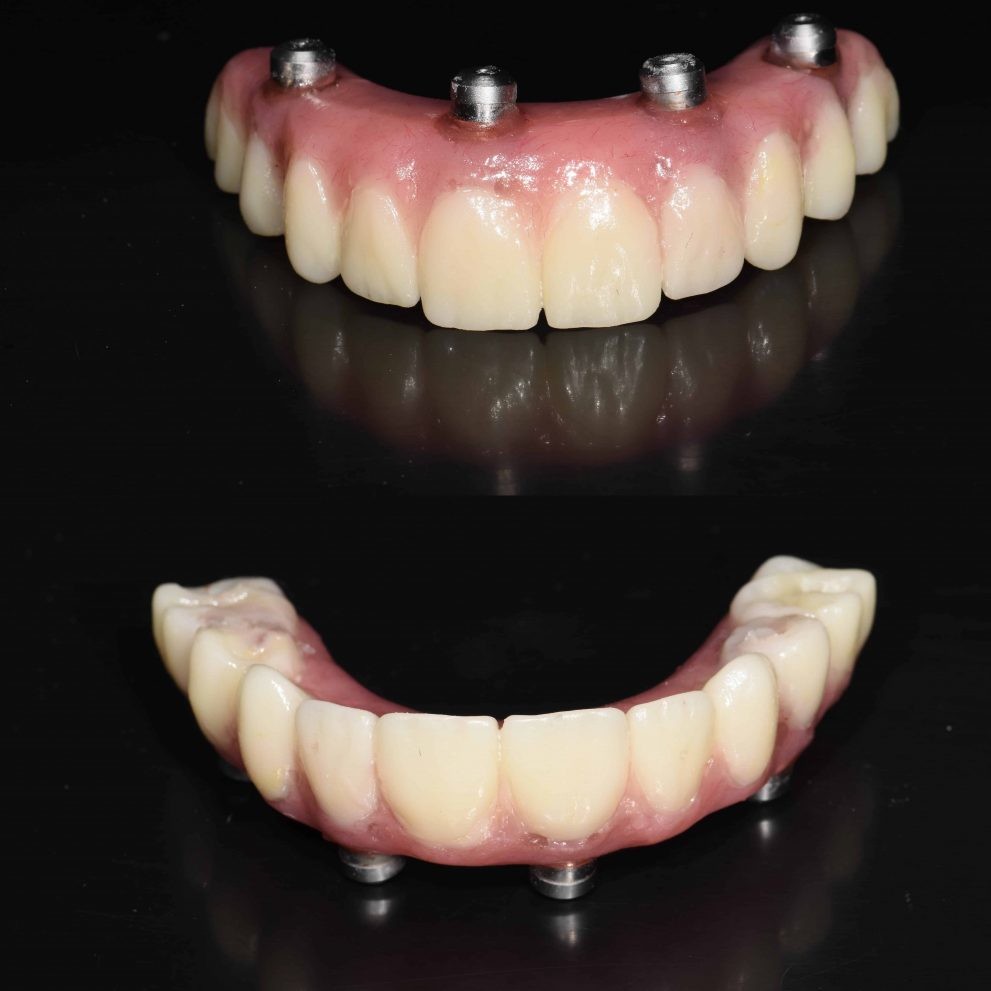

Yes it is possible to get a whole new set of teeth

Struggling with dental issues can be painful and stressful. If you’ve been dealing with tooth loss and wish you could have a new set of teeth, implant surgery can make this happen.

Dental implants have been in use for decades now and have an excellent track record. These teeth act just like your regular teeth so you have no food restrictions and they don’t need a complicated maintenance routine, just good oral hygiene practices and routine check-ups will suffice to keep them in good shape.

Can I have all my teeth pulled and get implants?

Yes, it is possible to get a whole new set of teeth. This is often the route chosen by those who have been dealing with dental distress for years.

Permanent dental implants are made with metals like titanium or zirconia. They are embedded well into the gum line and act just like the roots of your teeth. Replacement teeth are then affixed onto these implants. Dental implants can last a lifetime and are considered to be a permanent solution for tooth loss. All-on-four and all-on-six dental implant surgeries can be done to give you a new set of teeth in just one jaw or your entire mouthful of teeth.

The experienced dentists at Dental Artistry are able to insert implants in your jaw and fix in a whole new set of teeth that are anchored firmly by the implants. Not only are these a permanent, more efficient solution but they also prevent bone loss or erosion and the consequent sagging of the face often associated with dentures.

How many implants are needed for a full mouth?

Dental Artistry offers the option of giving you a full set of teeth with just four sets of implants. This surgical procedure is called all on four. One implant can hold in place multiple teeth. Sometimes your dentist may recommend that you have six implants instead of six, this is called the all on six procedure. Your dentist will advise how many implants are best for your needs.